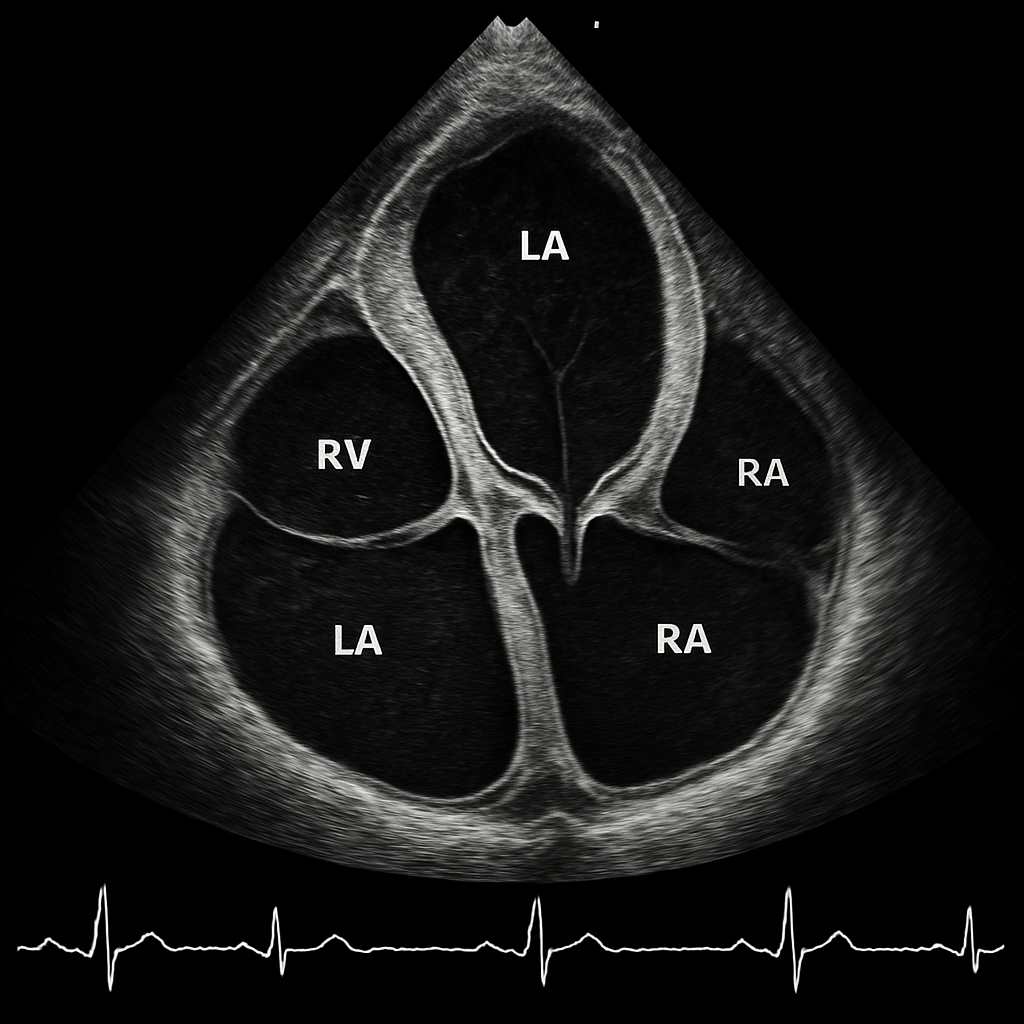

Echo — Subcostal Four-Chamber

Transthoracic echocardiogram subcostal four-chamber view showing all chambers from a subxiphoid approach. Liver visible at top of image.

ULTRASOUND AI Generated 2026-03-16

Subcostal Four Chamber

2D B-mode TTE, subcostal 4C view. Liver at near field, then heart with all four chambers.